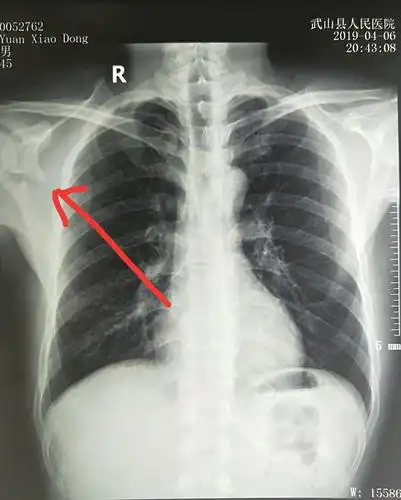

x线片示右肩胛骨粉碎性骨折,移位严重.